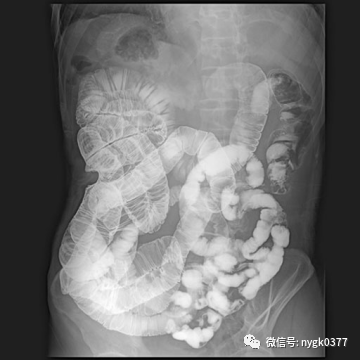

02、消化系统检查功能

1、ERCP检查(全新床体多中心倾斜设计,专用限束模式)

2、消化道特殊造影影

近期我院引进日本岛津 C200多功能影像中心系统,该设备拥有性能完善的影像链系统,保证了其以很低的剂量得到优质的图像。配置的高性能动态平板探测器系统,使其图像质量更加优越。模块化设计理念使其功能更加丰富,覆盖了骨科、消化科、儿科、妇科、泌尿、等多科室应用。床体多中心运动设计,使其能更好的完成泌尿造影、ERCP、输卵管造影等应用需求。突破性的功能设计延伸到骨密度检查、金属关节置换周边图像采集、DSA等图像采集需要。